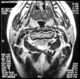

Compensatory hypertrophy with contralateral neural arch deficiency

Enlarged vertebral pedicle